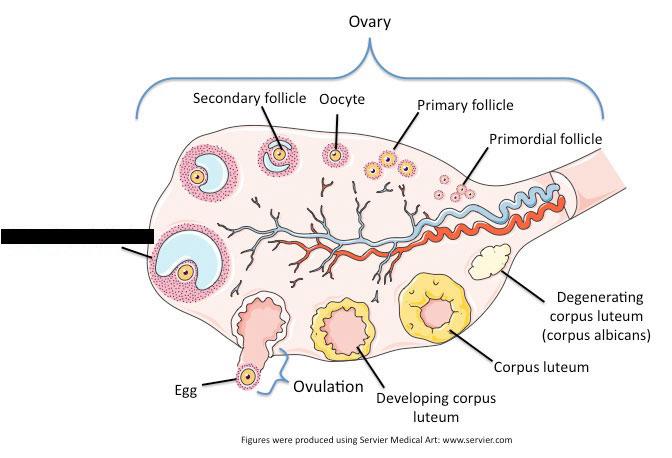

Corpus luteum

Mature (=Graafian, = antral) follicle

Ovary

Primordial/primary/secondary follicle